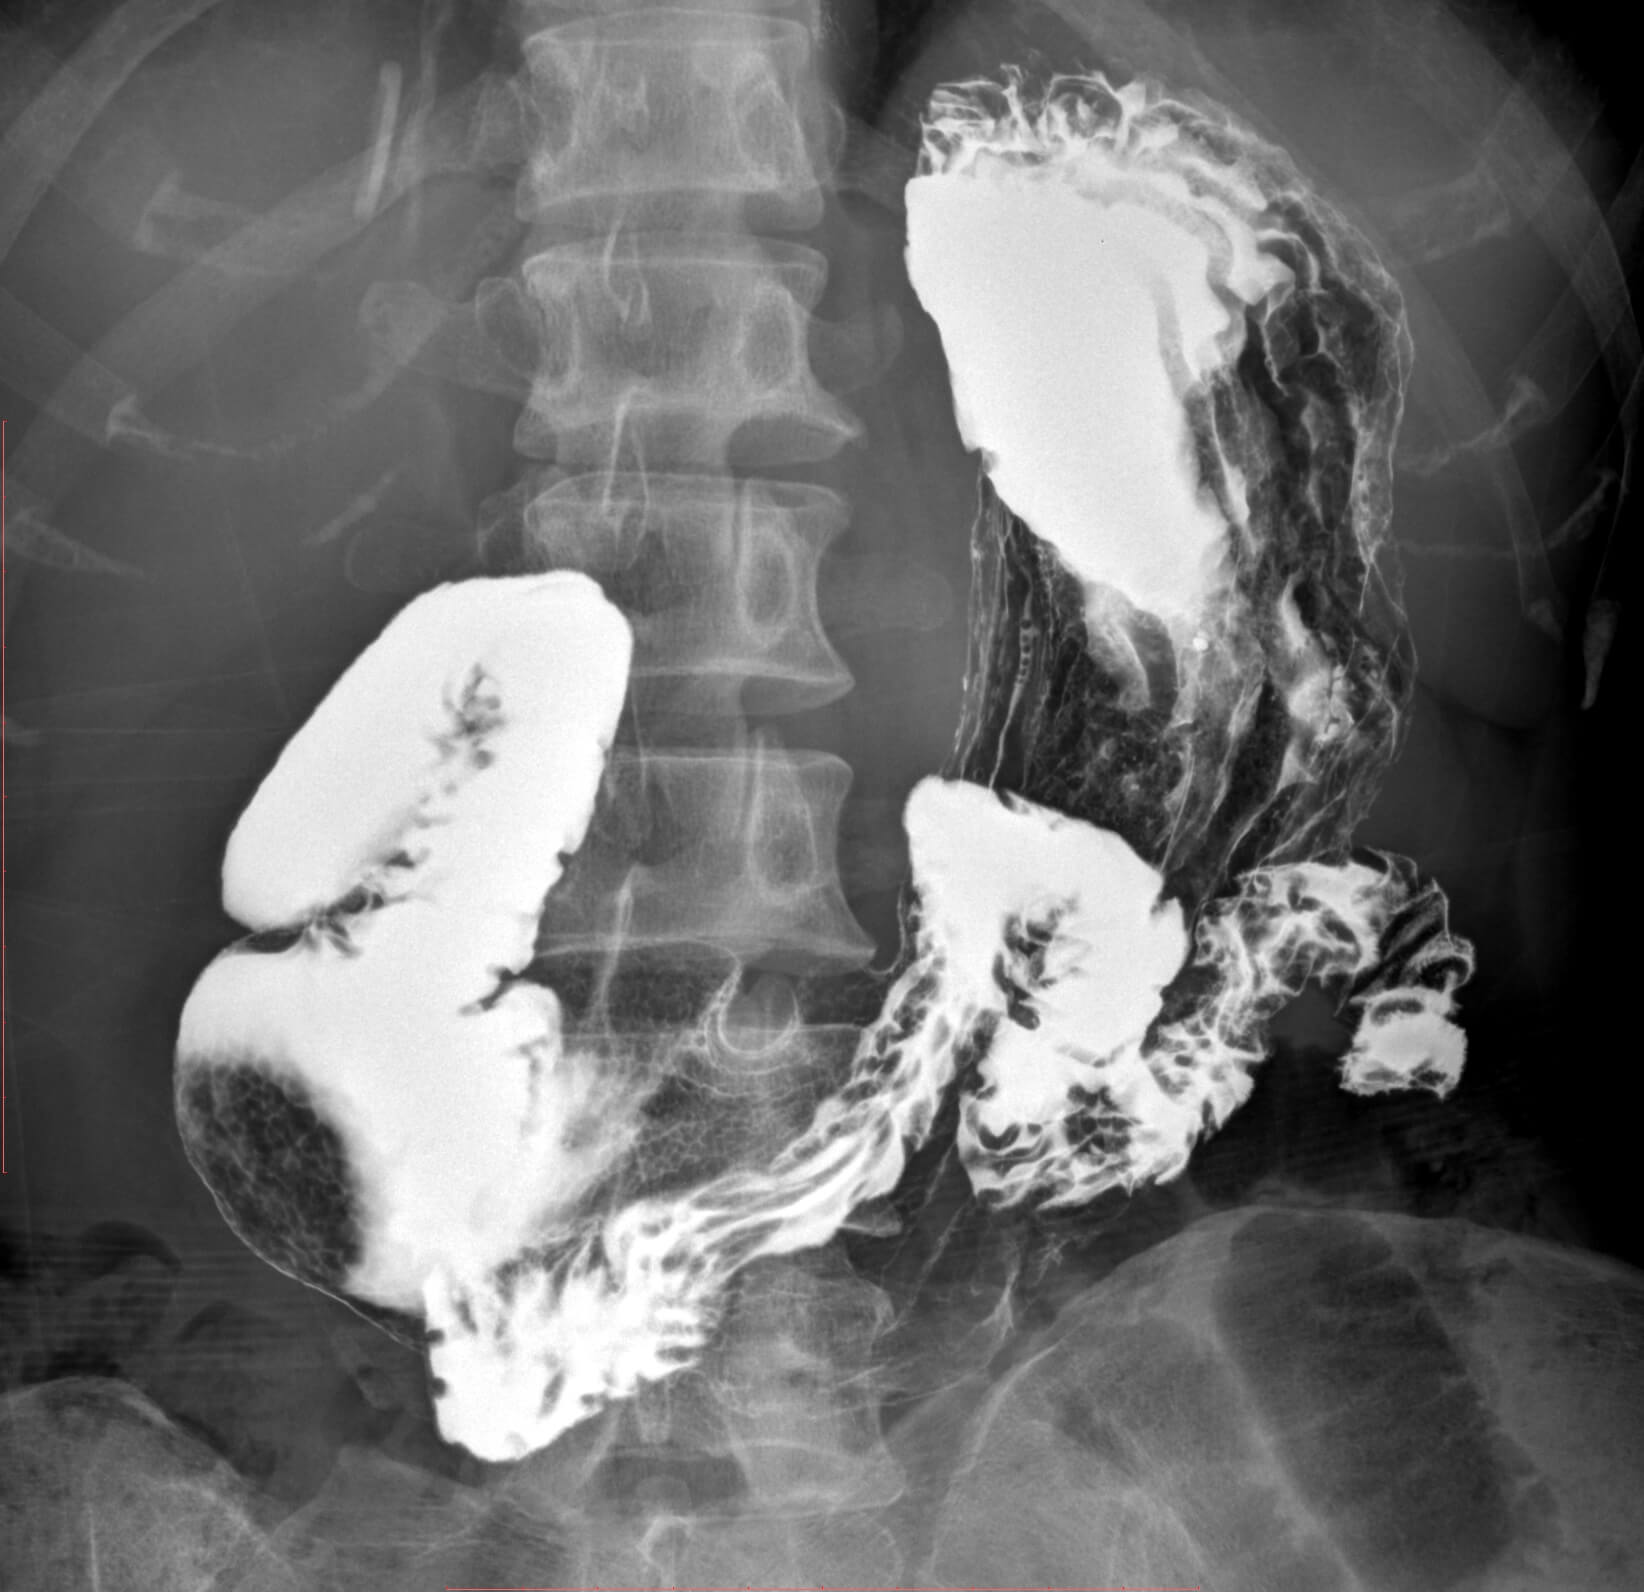

• Wide clinic applications

• Clever post processing of fluoroscopic image